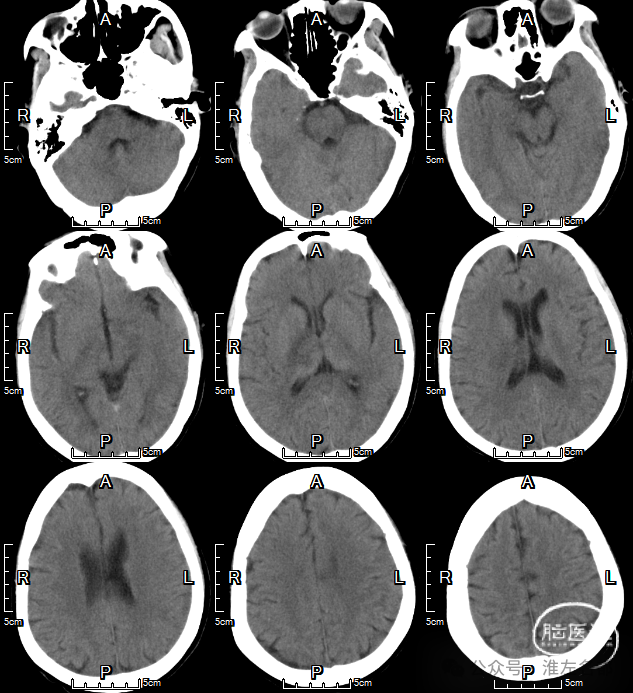

急诊多模式CT

2024-9-23 07:50

CT平扫:双侧丘脑低密度肿胀,直窦-大脑大静脉血栓高密度。

CT平扫(矢状位薄层重建):直窦-大脑大静脉-大脑内静脉-下矢状窦急性血栓高密度征。

CTV:左侧横窦-乙状窦细小,右侧横窦充盈缺损,深部静脉系统未见显影,上矢状窦显影不清晰。

2024-1-26 术后即刻

CT平扫:双侧丘脑静脉梗死区域造影剂染色。

2024-1-27 术后第2日

CT平扫:右侧丘脑静脉梗死区稍高密度。

CTV:上矢状窦、直窦、右侧横窦-乙状窦再通显影,右侧横窦局部管腔狭窄明显。

2024-10-2 术后第7天

CT平扫:双侧丘脑病变范围明显改善。

2024-10-14 术后第19天

CT平扫:仅见右侧丘脑和内囊少许低密度影。